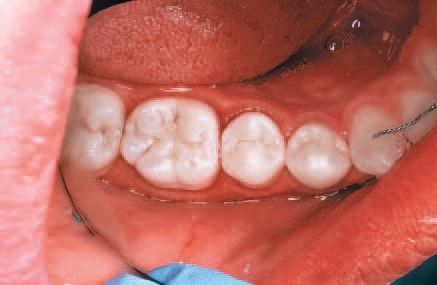

Research supports the use of the system on interproximal lesions from E1-D1, and recently the American Dental Association announced that resin infiltration of incipient smooth surface lesions is now covered by a 2013 CDT Code classification (D2990) to allow for accurate coding and billing for this new technology.16 A 20-year-old male presented for routine dental care, including prophylaxis, oral exam and radiographs.

An interproximal lesion was noted on the bitewing on the distal proximal surface of tooth No. 29 (Figs. 3 and 4). The patient was informed of the diagnosis and his options for treatment, which ranged from monitoring the lesion over time to prepping and restoring in a traditional method. We also discussed with him a new technology that fills, reinforces and stabilizes demineralized enamel without removing healthy tooth structure and arrests the progress of the proximal lesion. The patient eagerly opted for the ICON infiltration concept.

No local anesthesia is necessary, but rubber dam isolation is recommended to assist in the success of the ICON resin infiltration procedure. Cleanse the isolated tooth with NaOCl or Consepsis and rinse thoroughly with a water spray and air dry. The teeth are separated using one of the enclosed plastic wedges, which will allow for the placement of the Proximal-Tip foil matrix delivery system. The wedge can be maintained interproximally during the entire procedure if necessary (Fig. 5).